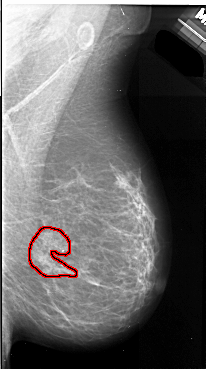

A_1056_1.LEFT_MLO

LEFT_MLO LINES 5521 PIXELS_PER_LINE 3001 BITS_PER_PIXEL 16 RESOLUTION 42 NON_OVERLAY

FILE: A_1056_1.RIGHT_MLO.OVERLAY

TOTAL_ABNORMALITIES 1

ABNORMALITY 1

LESION_TYPE MASS SHAPE IRREGULAR MARGINS ILL_DEFINED

ASSESSMENT 4

SUBTLETY 5

PATHOLOGY MALIGNANT

TOTAL_OUTLINES 1

BOUNDARY